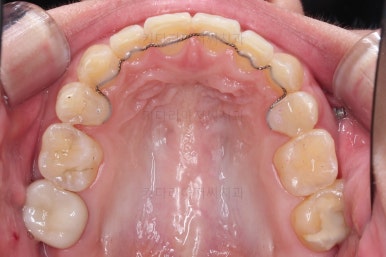

초진 시 입안의 모습입니다.

전반적으로 치열이 삐뚤고, 특정 앞니는 톡 튀어나가 미적으로 좋지 못한 상황이었습니다.

이갈이, 이악물기 습관도 있어서 앞니는 삐뚤어진 채로 치아가 많이 갈려있는 상황이었습니다.